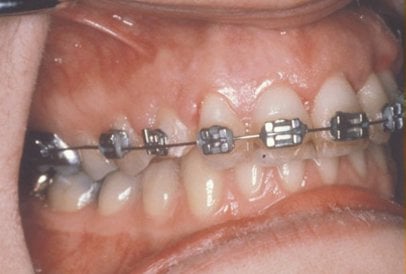

In cases where the eyeteeth will not erupt spontaneously, the orthodontist and oral surgeon will work together to get these teeth to erupt. Each case must be evaluated on an individual basis, but treatment will usually involve a combined effort between the orthodontist and the oral surgeon. The oral surgeon will expose and bracket the impacted eyetooth.

The goal is to erupt the impacted tooth and not to extract it. Once the tooth has moved into its final position, the gum around it will be evaluated. In some circumstances, there may be some minor “gum surgery” required.

Exposure and Bracketing of an Impacted Cuspid

What to expect from surgery to expose & bracket an impacted tooth

The surgery to expose and bracket an impacted tooth is a very straightforward surgical procedure that is performed in the oral surgeon’s office. For most patients, it is performed using laughing gas and local anesthesia. In selected cases it will be performed under IV sedation if the patient desires to be asleep, but this is generally not necessary for this procedure. If the procedure only requires exposing the tooth with no bracketing, the time required will be shortened by about one half. These issues will be discussed in detail at your preoperative consultation with your doctor.